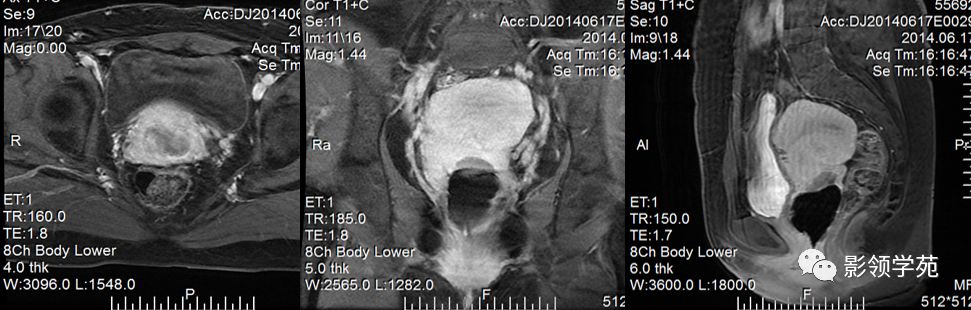

宫颈癌MRI表现

宫颈癌可表现为类圆形或不规则形肿块,在T2WI上表现为均匀或欠均匀的高信号,与正常宫颈基质及宫旁脂肪形成良好的自然对比。

MRI

- Ⅰ期肿瘤:侵犯宫颈基质,T2WI等信号肿块,宫颈管扩大及宫颈纤维基质中断

- Ⅱ期肿瘤:宫颈增大,宫旁肿块或宫旁脂肪组织内出现异常信号的粗线状影

- Ⅲ期肿瘤:侵犯至阴道下部,外延至盆壁,或出现肾积水。

- Ⅳ期肿瘤:膀胱壁或直肠壁低信号中断,膀胱壁或直肠壁增厚或腔内肿块。

DWI:局限性高信号,癌组织ADC值<癌旁组织<小于正常宫颈组织

IIB期